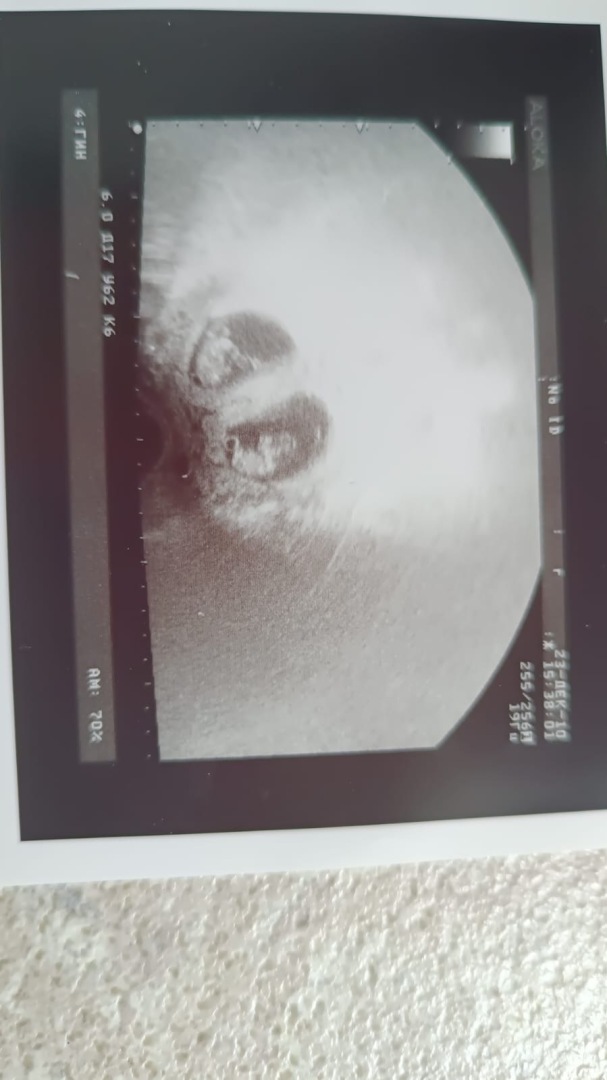

2. Пункция фолликулов: Из яичников извлекают созревшие яйцеклетки с помощью тонкой иглы под контролем УЗИ.